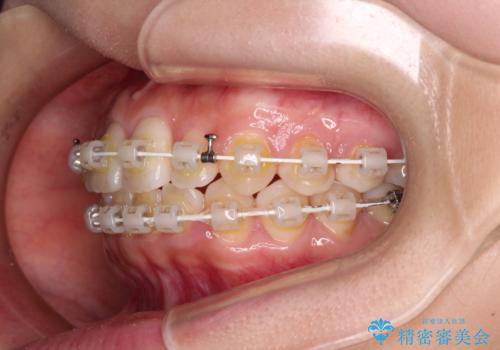

- 矯正装置

- 審美装置

治療方法としては、マウスピース矯正(インビザライン)でもワイヤー矯正でも、何でも対応可能ですが、自己管理の煩わしさがなく、治療期間の目処を立てやすい表側のワイヤー矯正にて治療を行うこととしました。

ワイヤー矯正は見た目や装置が当たることでの痛みを気にされる方が多いですが、月1回来院して処置をしてもらうだけで歯並びが整うため、大変お勧めです。